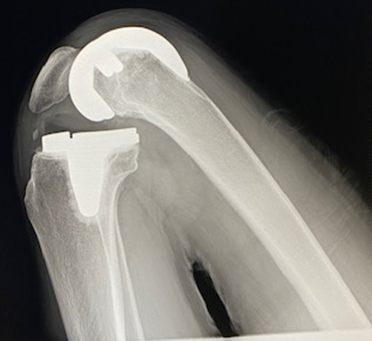

レイクタウン整形外科病院の人工膝関節センターは、加齢による膝の症状を診療し、特に人工膝関節置換術を専門的に行ってまいります。また、センター長の金山医師がメーカーとタッグを組み開発したプレカットトライアルや、膝リハビリクッション(いずれも特許取得済み)を使用することで、150°の屈伸も可能にする治療を目指します。

変形性膝関節症(へんけいせいひざかんせつしょう)

変形性膝関節症は、膝の関節が長年の使いすぎや加齢によってすり減り、痛みや動きの制限が生じる病気です。

膝関節は骨と骨がスムーズに動くために、軟骨というクッションのような組織に覆われています。しかし、年齢や過度な運動、肥満などの要因でこの軟骨が徐々にすり減り、骨同士が直接こすれ合うようになります。その結果、膝に痛みや腫れなどの症状が出現し、膝を曲げ伸ばしするのが難しくなることがあります。

初期の段階では、運動後に膝が痛くなる程度ですが、進行すると歩くのが困難になることもあります。

大腿骨内顆骨壊死症(だいたいこつないかこつえししょう)

大腿骨内顆骨壊死症は、膝関節に近い大腿骨の内側部分(内顆)が血流不足により壊してしまう病気です。

骨は通常、血液によって栄養が供給されているため健康に保たれていますが、何らかの原因で血流が途絶えると、その部分の骨が死んでしまい、痛みや関節の機能に問題が生じます。 この病気では、膝の内側に痛みを感じることが多く、最初は運動や歩行時に痛みが出ますが、進行すると安静時にも痛みが続くようになります。

膝の動きが悪くなり、日常生活で膝の曲げ伸ばしや歩行が困難になることもあります。

大腿骨内顆骨壊死症の原因ははっきりしていないこともありますが、ステロイド薬の使用やアルコールの多飲、外傷、または血流障害が関与していると考えられています。

リウマチ性膝関節炎(リウマチせいひざかんせつえん)

リウマチ性膝関節炎は、膝の関節が体の免疫システムの異常によって炎症を起こし、痛みや腫れ、関節の変形が生じる病気です。

本来、免疫は体を守るために働くのですが、リウマチの場合、誤って自分自身の関節を攻撃してしまいます。このため、膝の関節を覆っている滑膜(かつまく)という部分が炎症を起こし、腫れて痛みを感じるようになります。

リウマチ性膝関節炎の特徴的な症状は、朝起きたときに関節がこわばることです。また、進行すると膝の動きが制限され、関節の形が変わってくることもあります。